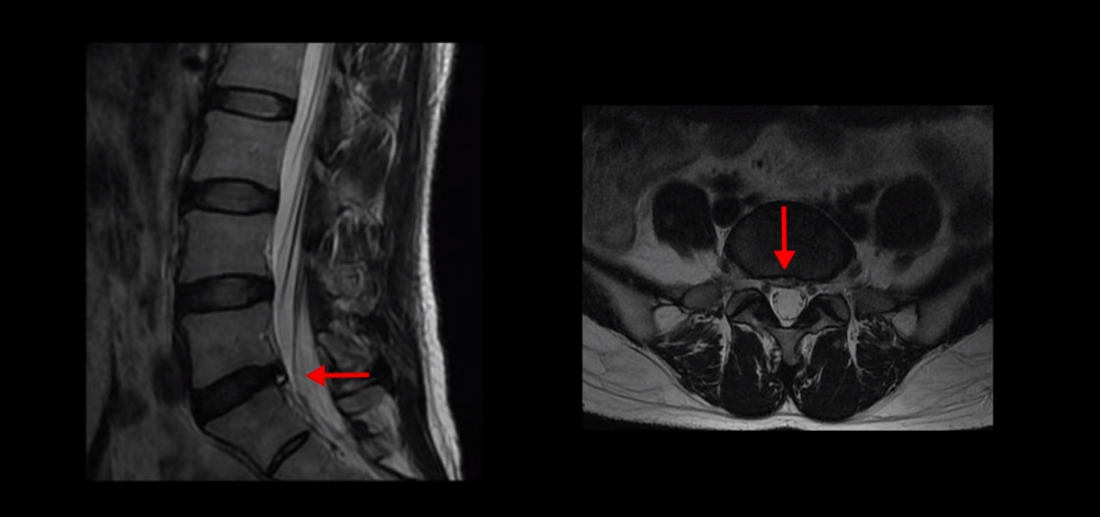

보시다시피 퇴행성 디스크가 있고 디스크 밀려 나온 게 아주 조금 보이기는 하지만 신경을 눌러서 심한 방사통을 일으킬 정도로 특히 양쪽 다리가 앉아도 서도 누워도 저릴 정도로 심하지 않습니다. 이렇게 디스크가 심해 보이지 않으면 허리, 엉덩이 통증과 양쪽 다리 저림 증상의 원인을 다른 원인, 특히 근육으로 의심해 봐야 하는데도 진료 받은 대부분의 정형외과, 신경외과, 통증의학과에서는 근육 문제는 얘기하지 않고 디스크 문제만 얘기하고 치료합니다.

이분의 증상과 MRI를 비교해 봐도 신경 문제가 아니라는 건 명확합니다. 일단 저렇게 가벼운 디스크 탈출이 심한 양쪽 다리 증상을 일으키기도 어렵고, 더군다나 디스크로 인한 신경 눌림은 일반적으로 누우면 줄어드니까 누워있으면 다리 저림이 조금이라도 줄어야 하는데 누워 있으면 오히려 더 심해집니다.

이 근육성 방사통이나 좌골신경통의 특징이 증상이 심한 사람들일수록 오히려 누워 있을 때 발끝까지 저린다고 하는 분들이 많습니다. 일반적인 디스크 증상과는 다른 증상입니다. 이렇게 MRI와 환자의 증상이 일치하지 않는데도 MRI에 보이는 아주 조그만 디스크 문제만 계속 치료하는 이유는 근육이 다리 저림을 일으킨다는 것을 인정하지 않는 의사들이 너무나 많기 때문입니다.